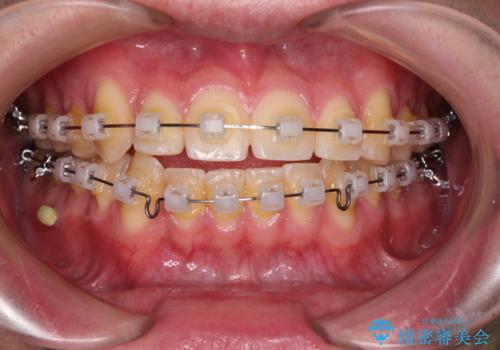

八重歯と前歯のクロスバイト ワイヤー装置で短期間矯正

- クリアブラケット

- 1年4ヶ月

上顎側切歯(前から2番目の歯)が内側に転位している歯列は、インビザラインでは排列が困難であることが多いため、期間を短く、より良い仕上がりとするため、ワイヤー装置にて矯正治療を行うこととしました。